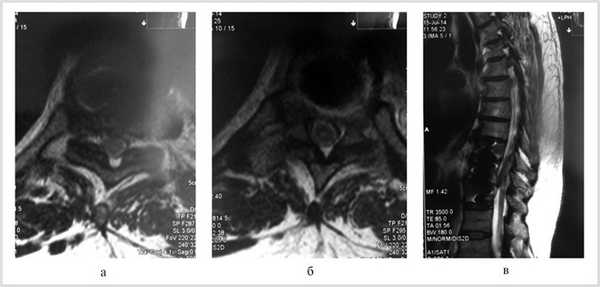

Проведена МРТ (рис. 2): компрессия спинного мозга устранена. Больной переведен в неврологическое отделение для восстановительного лечения.

Рис. 2. Магнитно-резонансные томограммы грудного отдела позвоночника (Т1 режим): в аксиальной (а, б) и сагиттальной (в) плоскостях через 2 нед после операции.